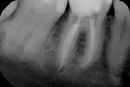

Я лечила каналы. Врач после своей работы, сделала снимок и увидела, что гуттаперча вышла за верхушку корня зуба, при том, что там еще и небольшая киста. Врач сказала, что чуть дольше поболит, и чуть дольше будет заживать. Переделывать не стала. Я переживаю, что могут быть последствия, так как планирую беременность.

Нужно ли перелечить, или такое часто бывает и это норма?

Как правило, выведение гуттаперчи за верхушку корня ведет к возникновению ответной реакции организма, возникновению периапикальных разряжений и развитию воспалительного процесса. Рекомендуется зуб перелечить, тем более при планировании беременности.